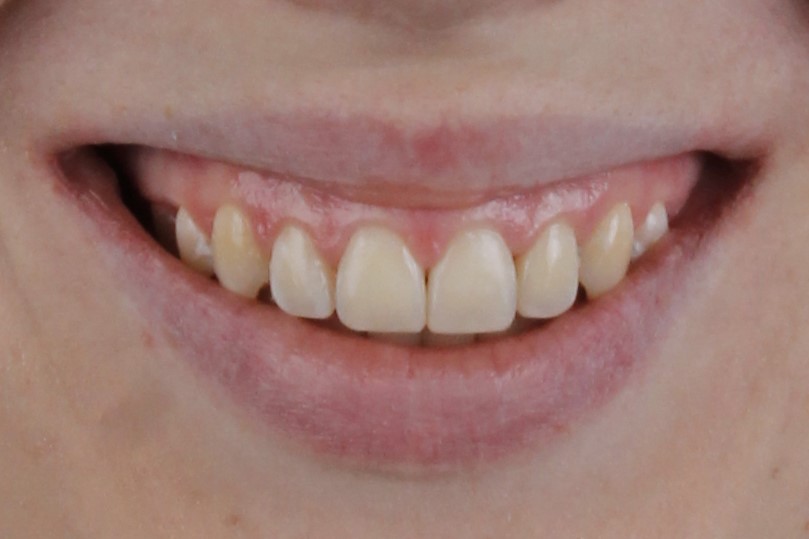

У меня никогда не смыкались зубы полностью и бепокоили клыки. Решила обратиться за консультацией к ортодонту. В завершении лечения понимаю, что это было самым моим лучшим решением-начать лечение на брекет-системе!

Мне так хотелось улыбаться красивой улыбкой, но я видела только свои острые клыки. Хочу сказать огромное спасибо за свою новую улыбку, потому что теперь я ощущаю гармонию, когда вижу себя в зеркале.